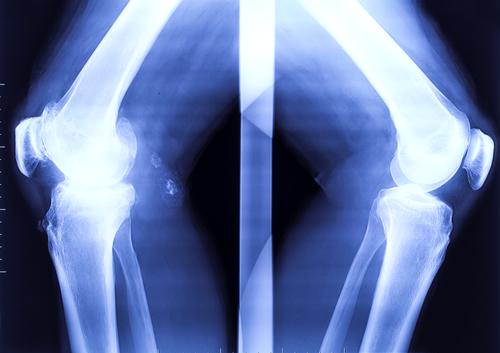

« Ces calcifications forment des ponts d’os entre les articulations. Le malade est peu à peu emprisonné dans un second squelette », précise l’association française sur la FOP sur son site Internet.

Jasmin Floyd a été diagnostiquée lorsqu’elle était petite. Elle souffre d’une fibrodysplasie ossifiante progressive (FOP), une maladie héréditaire sévèrement invalidante du tissu conjonctif, caractérisée par une ossification progressive des muscles, tendons, ligaments et autres tissus mous. Elle est liée à une mutation du gène ACVR1.